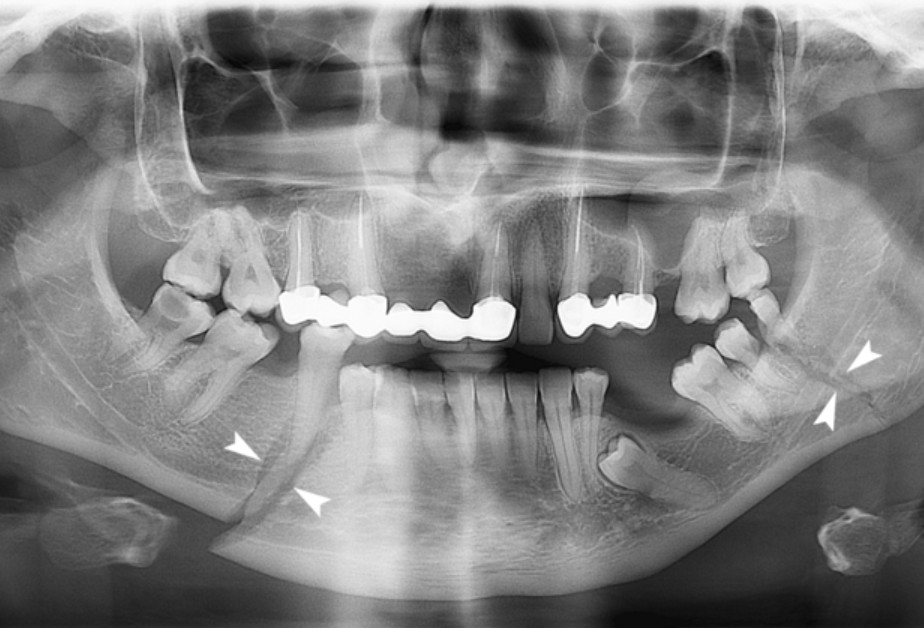

Imaging tests are used to confirm the type, location, and severity of the fracture:

- CT scans – the most accurate and commonly used method, providing detailed images of bones, soft tissues, and blood vessels

- X-rays – useful for examining bones, they are less detailed than a CT scan but helpful for nasal or jaw fractures. This thorough assessment ensures an accurate diagnosis and helps guide the most appropriate treatment plan for each patient.